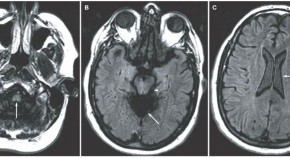

Arterial dissections are one of the most common forms of vascular lesion to affect the cervical carotid and vertebral arteries, second only to atherosclerosis. Arterial dissections are often caused by sudden or unusual stretching of arteries in the neck or head, and can occur as a complication of chiropractic and other neck manipulations. In this article, Louis Caplan reviews the underlying causes and clinical features of dissections of brain-supplying arteries and outlines the current recommendations for treatment of these lesions.